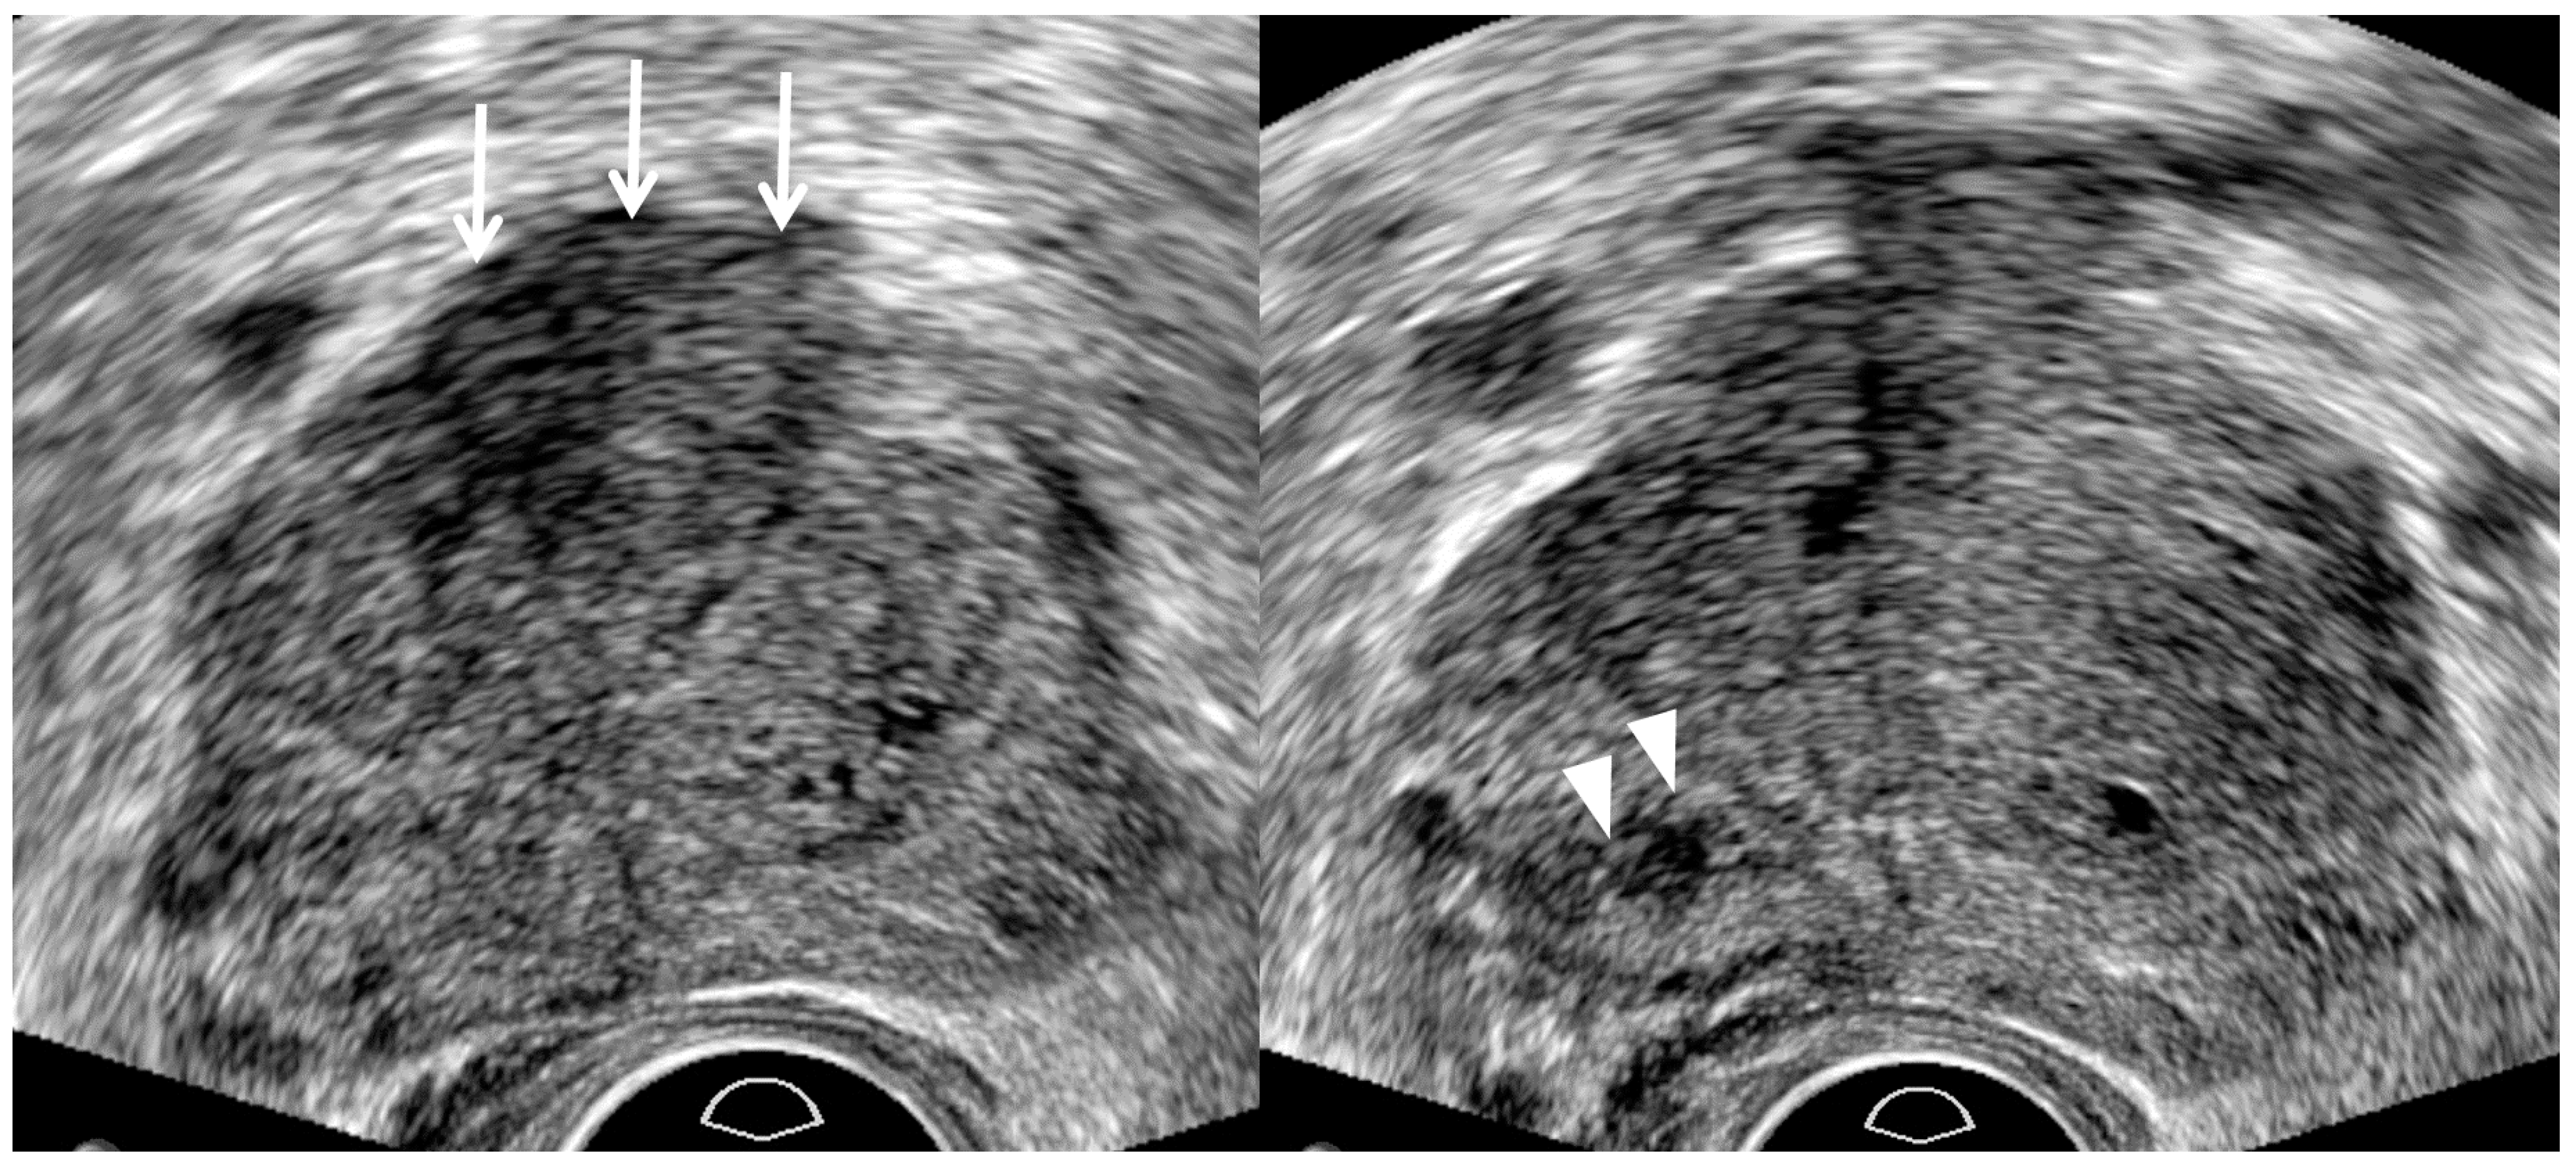

| TRUS-Guided Biopsy | Old Biopsy Techniques | New Biopsy Techniques |

|---|---|---|

| Central tumor targeting | Yes | Yes |

| Peripheral tumor targeting | No | Yes |

| Number of target cores | Oligo-cores (1–3) | Multi-cores (4–6) |

| Systematic biopsy | Yes | Yes, but no in T3/T4 cancers |